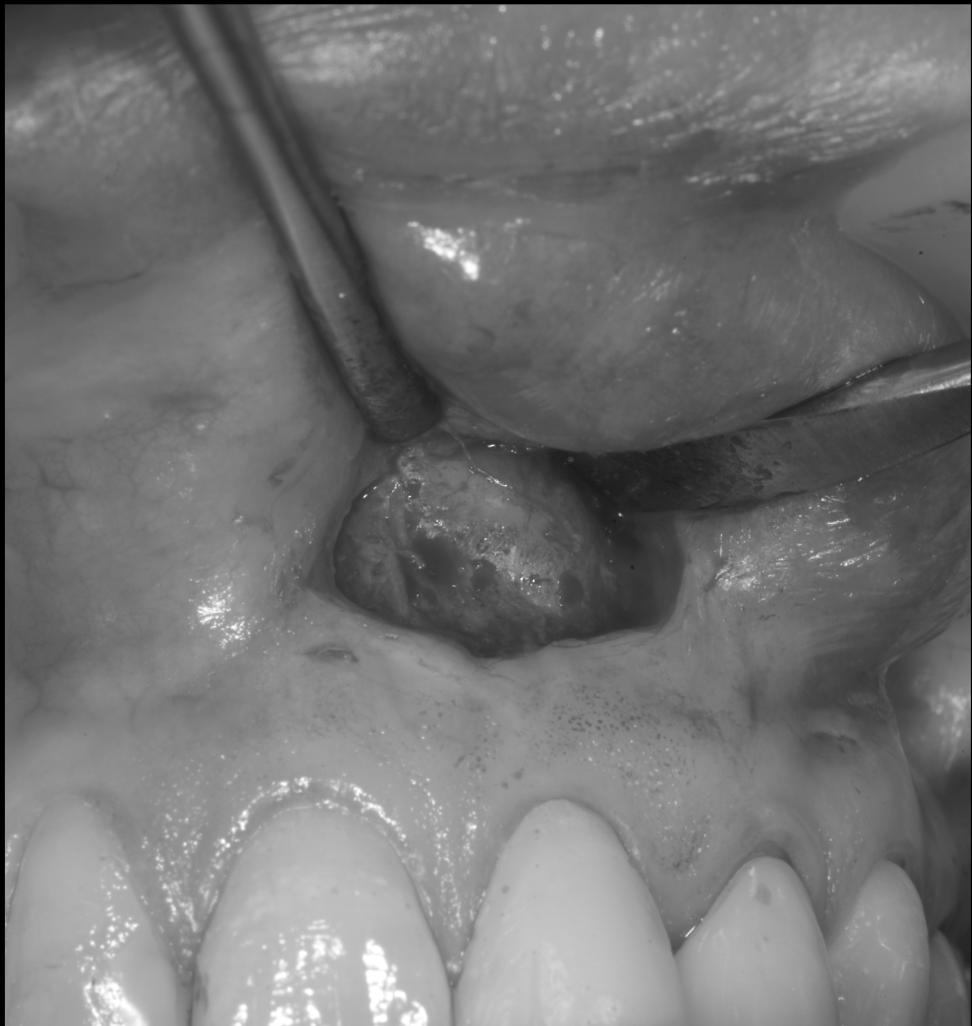

上唇の腫脹を認め、CT検査にて根尖部に嚢胞様透過像を認めた。左上の前歯が不自然に大きく噛み合わせが強くなっていたことがフレアアップの一因と考える。精密根管治療を行い、感染経路を遮断したのち歯根端切除術にて嚢胞を摘出した。

治療中